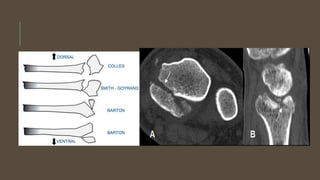

Clasificación:

-Colles

-Barton

-Smith

-Chofer

-Die-punch

Tac: nos permite la identificación de fragmentos

intrarticulares que en las rx no se observan

RADIOLOGÍA

FRACTURA DE BARTON

Se define como una fractura-subluxación articular desplazada e

inestable del radio distal, con desplazamiento del carpo y de los

fragmentos de las fracturas.

La fractura de Barton o fractura marginal dorsal se produce de forma

similar a la fractura de Colles.